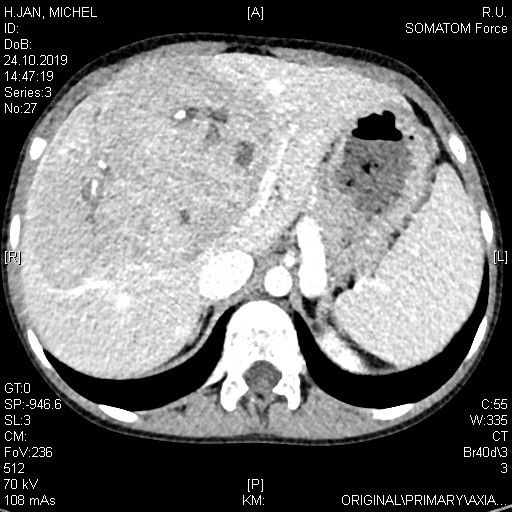

3- jähriger Junge mit stattgehabter Pfortaderthrombose (Verschluss der Pfortader).

Zustand nach Anlage eines Meso-Rex Shunts. Aktuell Größenzunahme der Milz und zunehmende Zeichen des Pfortaderhochdrucks. Sonographisch wurde dann der Verdacht auf eine Stenose (Verengung) der Shunts gestellt. In der Angiographie mit einem Zugang über Milz zeigte sich die vermutete Stenose (Pfeil in Bild A). Es wurde dann ein Stent eingebracht und mittels Ballon dilatiert (B). In der Kontrolle zeigte sich ein gutes Ergebnis mit Beseitigung der Engstelle. Dem Patienten ging es rasch besser.